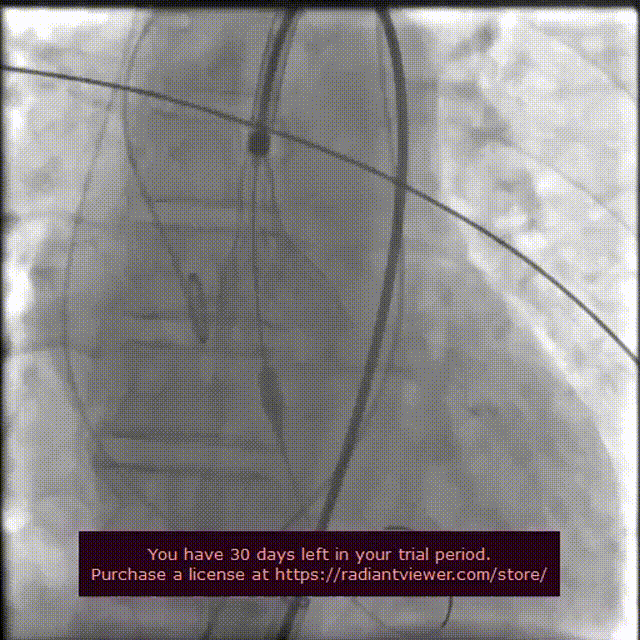

第二次定位释放

第二次完全释放